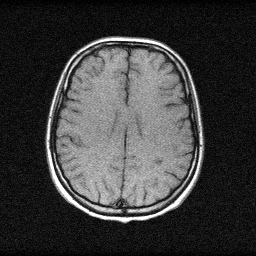

Reconstruction Gallery — 4 Scenes × 3 Scenarios

Method: CPU_baseline | Mismatch: nominal (nominal=True, perturbed=False)

Ground Truth

Reconstruction

Mean PSNR Across All Scenes

| Scene | I (PSNR) | I (SSIM) | II (PSNR) | II (SSIM) | III (PSNR) | III (SSIM) |

| scene_00 | 16.369188751529634 | 0.3769596313670564 | 28.91599361455386 | 0.8937325593738555 | 43.0888232643681 | 0.9970601105022431 |

| scene_01 | 17.02984109629589 | 0.5076141905187631 | 29.54697836453365 | 0.9088858192167282 | 44.00498178524224 | 0.9974331602373123 |

| scene_02 | 19.876634796830935 | 0.5132084125883123 | 29.296469693787934 | 0.8901788054246903 | 45.80916505985154 | 0.9983439806976319 |

| scene_03 | 16.209230008064964 | 0.3451008090497886 | 28.211197909256423 | 0.8836538261470794 | 42.81516446798818 | 0.997371546825409 |

| Mean | 17.371223663180356 | 0.4357207608809801 | 28.99265989553297 | 0.8941127525405883 | 43.929533644362515 | 0.9975521995656491 |